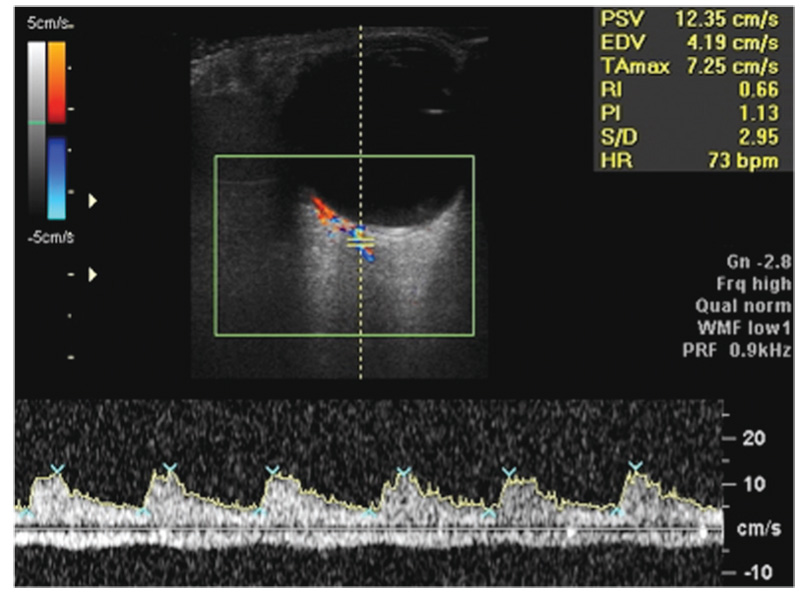

Fig. 2. The Doppler spectral analysis of blood flow velocities in the central retinal artery after normalization of intraocular pressure (Vsyst = 12.7 cm/s, Vdiast = 3.5 cm/s)

Рис. 2. Доплеровский спектр кровотока в центральной артерии сетчатки и центральной вене сетчатки после нормализации офтальмотонуса (Vsyst = 12,7 см/c, Vdiast = 3,5 см/c)